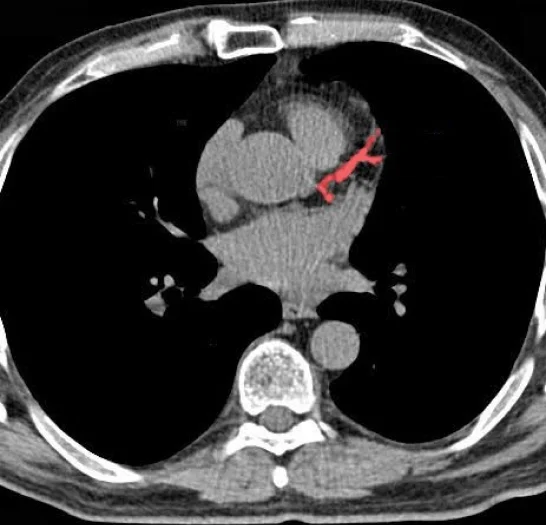

Cardiac CT Annotation & Segmentation

Pareidolia Systems provides specialized cardiac CT annotation and segmentation, labeling coronary arteries, plaques, calcifications, chambers, and vessels across CTA, CECT, and NCCT scans. Each dataset undergoes rigorous expert validation, ensuring clinically accurate data that empower AI-driven cardiac risk prediction and heart disease detection systems